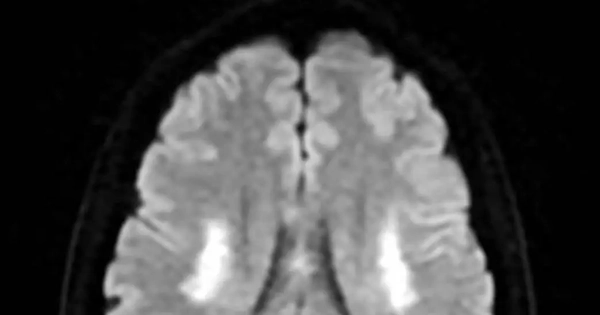

Người phụ nữ 42 tuổi, đã có hai con trai sinh thường, bất ngờ nhập viện trong tình trạng nói đớ và được chẩn đoán nhồi máu não chỉ vài ngày sau khi tiêm thuốc kích thích buồng trứng trong quy trình thụ tinh trong ống nghiệm.